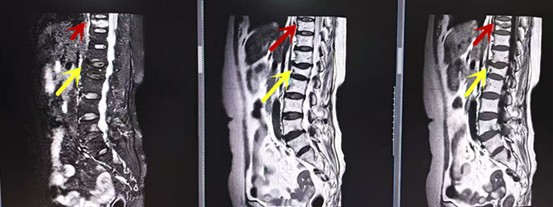

利器三:MRI(核磁共振)

MRI利于磁場和射頻脈沖使體內(nèi)的氫原子核發(fā)生磁共振現(xiàn)象而產(chǎn)生的圖像,對軟組織的分辨率很高,對于脊髓、椎間盤、神經(jīng)、血管、韌帶、骨髓、腰部肌肉及周圍軟組織有很好的顯示效果,可以清晰的顯示腰椎間盤突出對硬膜囊、神經(jīng)根壓迫程度,以及骨折是陳舊還是新鮮,同時在脊髓病變(如脊髓損傷、髓內(nèi)出血或腫瘤)、椎管內(nèi)膿腫/血腫、椎旁肌肉軟組織病變等方面也具有優(yōu)勢,但是檢查時間較長,部分患者可能因體內(nèi)金屬植入物(如心臟起搏器、人工耳蝸等)而無法進(jìn)行檢查。

箭頭提示腰椎管內(nèi)腫瘤

紅色箭頭提示新鮮骨折,黃色箭頭提示陳舊性骨折